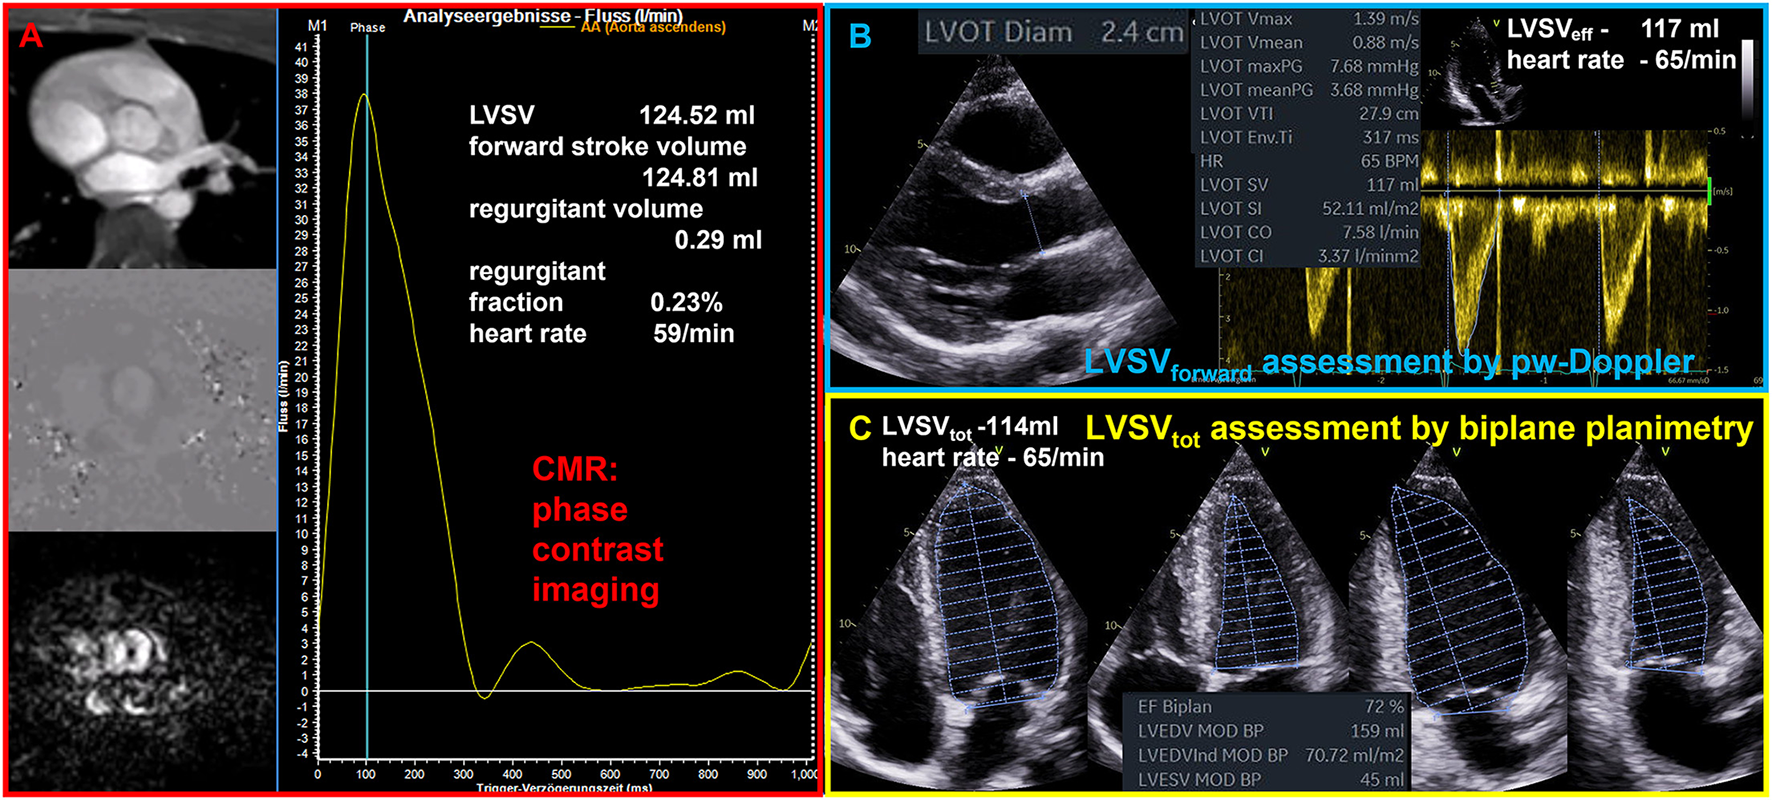

The quantitative assessment of LV volumes (LVEDV and LV end systolic volume - LVESV) by TTE—especially in comparison to cardiac magnetic resonance tomography (CMR)—is an ongoing debate (19, 20). A significant underestimation of LVEDV by native 2D echocardiography is often reported compared to CMR, which is considered as the gold standard of cardiac volume assessment. Comparable or even overestimated LV volumes determined by native 2D echocardiography in comparison to CMR were only reported in a minority of studies (19). LV volume differences between both modalities are not induced by the modalities per se, but rather by the consequences of methodological inaccuracies. Thus, equivalent approaches should be compared, such as biplane measurements by TTE and CMR, or short axis LV assessment by respective sectional slices within a 3D-TTE data set and CMR short axis packages. Whereas, the main echocardiographic problem is the delineation of the LV endocardium including the trabecula into the LV cavity (19), there are other reasons for measuring larger LV volumes by CMR such as different orientation of 2- and 4-chamber view (2, 4 ChV) in comparison to TTE (in CMR studies 2 ChV is often perpendicular to the 4 ChV instead of a 60° rotation difference in TTE studies.) and lower heart rates in CMR than in the comparable TTE documentation at rest. The comparability of LVSVeff measurements between echocardiography and CMR (see Figure 1) as well as between echocardiographic modalities (see Figure 2) are illustrated during normal conditions. With respect to the accurate cardiac volume assessment proposed in patients with valvular regurgitations by recent recommendations (4), approaches performed by CMR can comparably be performed by echocardiography providing a high level of standardization and image quality.

Figure 1

Illustration of comparable quantitative assessment of left ventricular stroke volume (LVSV) by cardiac magnetic resonance tomography (CMR) and echocardiography. (A) Phase contrast imaging and assessment of forward flow through the aortic valve by CMR phase contrast imaging. (B) Assessment of forward LVSV through the aortic valve by pulsed wave (pw) Doppler (LVSVforward); LVSVforward is the effective LVSV (LVSVeff) as well as the total LVSV (LVSVtot) during normal conditions. (C) Assessment of LVSVtot by biplane planimetry.